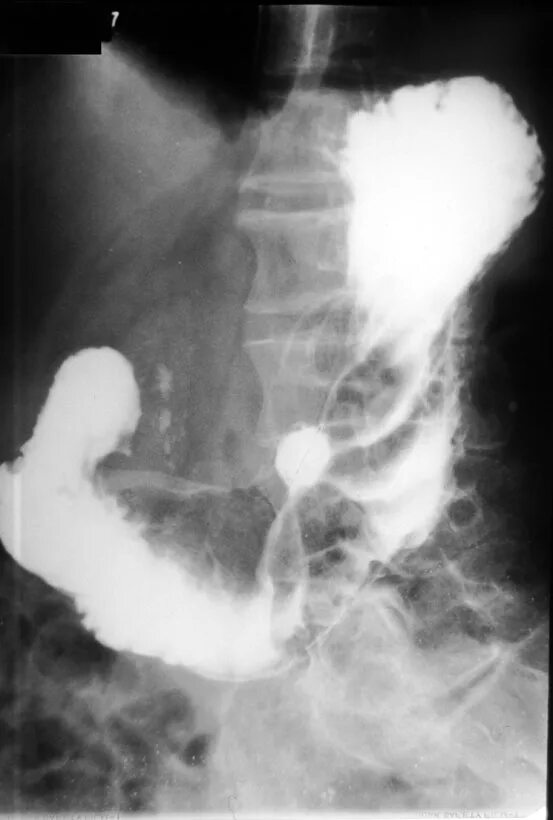

Рентгеноскопия жкт